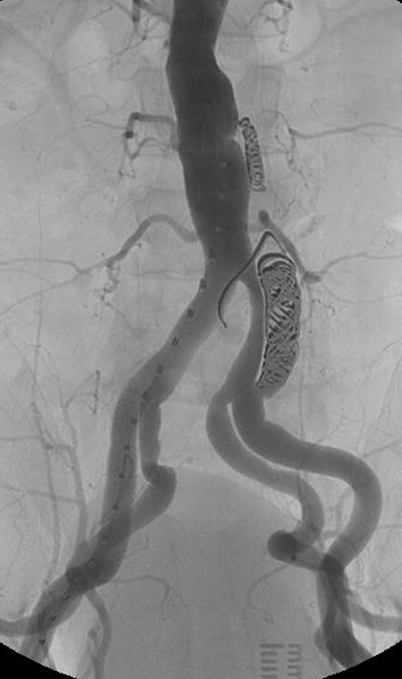

★ WeFlow-EndoSeal™假腔栓塞系统(N=11)

持续假腔血流被认为是TEVAR/EVAR术后动脉瘤样退变的原因。EndoSeal™系统是中国人民解放军总医院第一医学中心血管外科郭伟教授团队自主研发的,一种用于假腔栓塞的设备,能有效阻断假腔回流,促进主动脉重塑。

临床试验早期结果:

纳入11例患者,7例完成术后30天内CTA随访

术后30天假腔100%部分血栓化,真腔直径扩大(12.09→14.53mm),假腔最大直径稳定

1例严重不良事件(术后113天内漏栓塞)